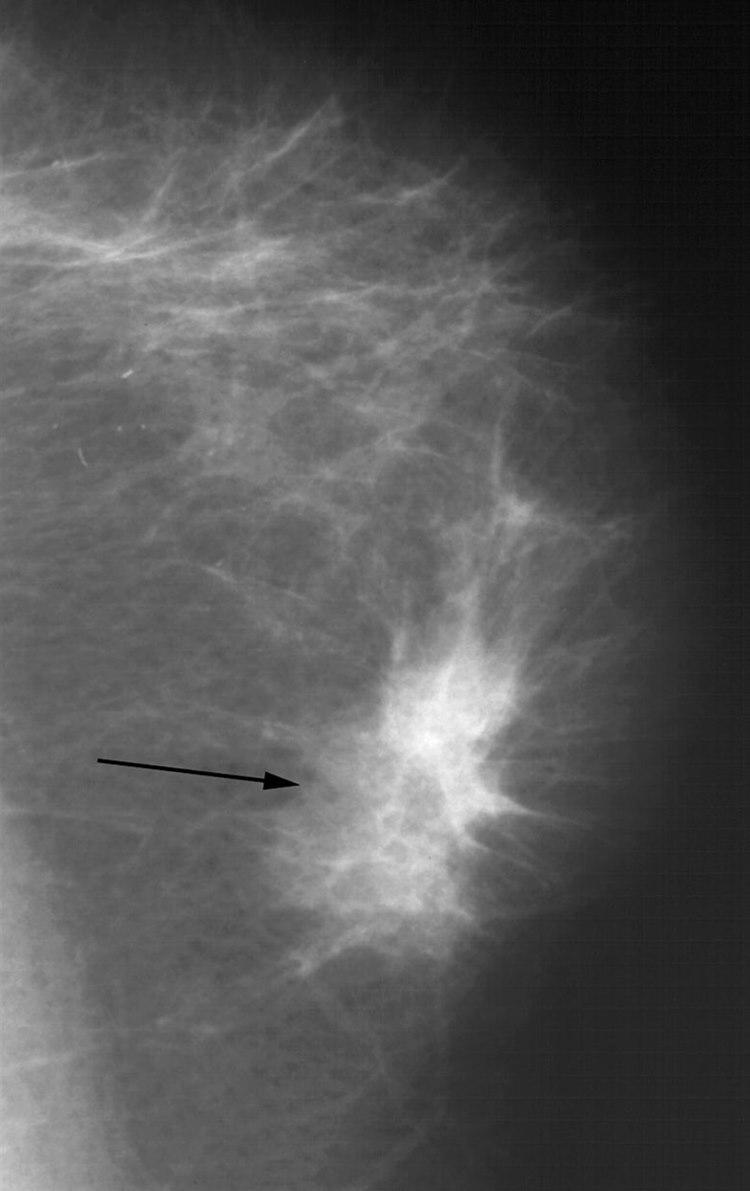

Røntgenbildet viser kjertler, melkeganger og bindevev mot en bakgrunn av fett. Ved typiske forandringer kan røntgenlegen skille godartet fra ondartet forandring. Mens godartede forandringer skyver normalt brystvev tilside når de vokser, kan ondartede forandringer vokse inn i omliggende brystvev. Utseende av svulsten og forkalkninger kan også gi viktig tilleggsinformasjon. Tidligere røntgenbilder av brystene er verdifulle til sammenligning når røntgenlegen vurderer de nye bildene. Supplerende ultralyd kan være avklarende, og gjøres vanligvis der det er unormale funn på mammografi. Hos noen tas en nåleprøve fra vevet i den mistenkelige forandringer for endelig avklaring.

Godartede fortetninger som cyster og bindevevsknuter (fibroadenomer) er vanligvis runde og klart avgrensede. Ondartede fortetninger er vanligvis uregelmessige med uklar avgrensning og innvekst i omgivende vev, ofte med økt antall blodkar. Forkalkninger kan ses som små spredte saltkorn (mikrokalsifikasjoner), og enkelte typer forkalkninger kan være uttrykk for kreft. Sannsynligheten for at det er ondartet, øker når forkalkningene er samlet. Forskyvning av tilgrensende brystvev og fortykkelse av hud kan også være krefttegn. En del forandringer i brystvevet kan være vanskelige å fortolke og krever tilleggsundersøkelser.